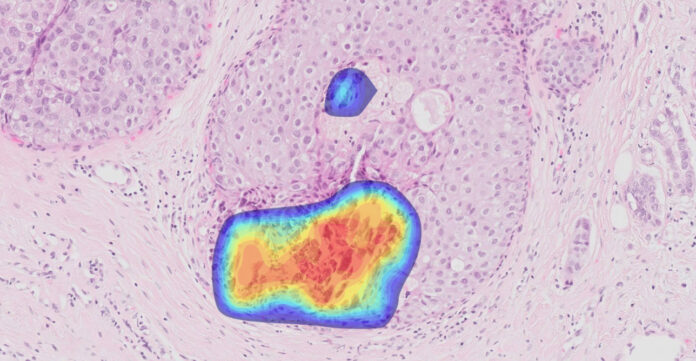

The research examined 104 real-world breast biopsy cases, including invasive and microinvasive carcinomas, ductal carcinoma in situ (DCIS), atypical lobular hyperplasia (ALH), and benign lesions. Three experienced breast pathologists reviewed each case both with and without the support of Ibex’s AI system. With the AI’s assistance, diagnostic accuracy increased from 97.1% to 100%, with previously missed precancerous lesions such as lobular neoplasia and microcalcifications successfully identified.

Ibex Breast, first launched in 2022, detects more than 50 malignant and benign tissue morphologies and is already in use by leading pathology labs worldwide. The platform was developed using a globally sourced dataset and trained on diverse slide images from different digital scanners. It is designed to support real-time diagnostic decisions, even in complex or borderline cases.